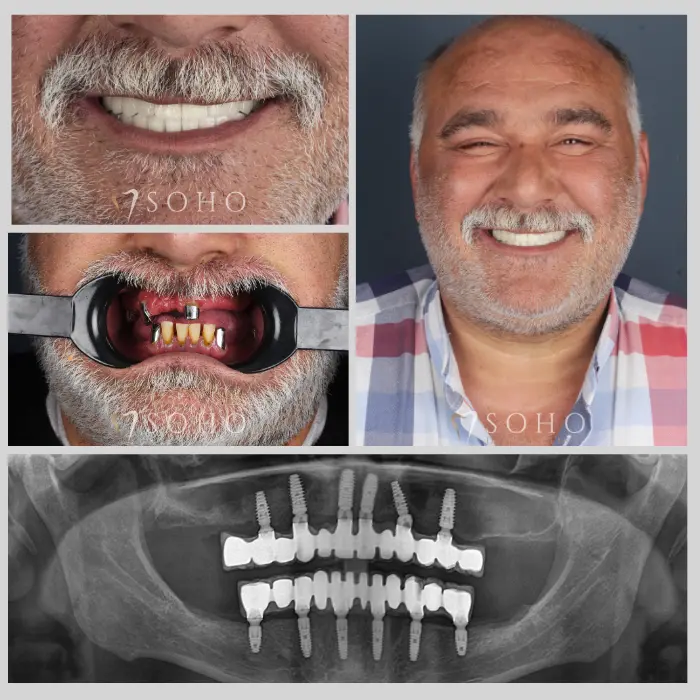

Real Patients. Real Smiles.

Explore the journey of our international patients through authentic visuals, elegant transformations, and moments captured inside Soho Dental Clinic. Let their stories inspire your own.

From First Visit to Final Smile.

Explore real patient stories captured in every transformation. These are more than smiles — they are renewed confidence, achieved with care and precision at Soho Dental Clinic.